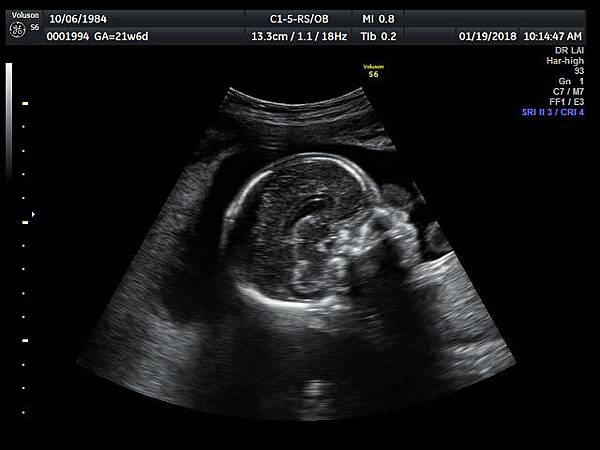

2. 冠狀切面(coronal plane):一般只能看到駢胝體genu 的部分,無法很完整的看整個駢胝體。

3. 要看完整的駢胝體,我的經驗是胎頭臉朝上比臉朝下好。(附圖 11~14)